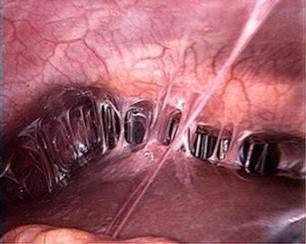

Legendary images need no history. What's the Diagnosis?

Spot Diagnosis?

Diagnosis?

What's the syndrome?